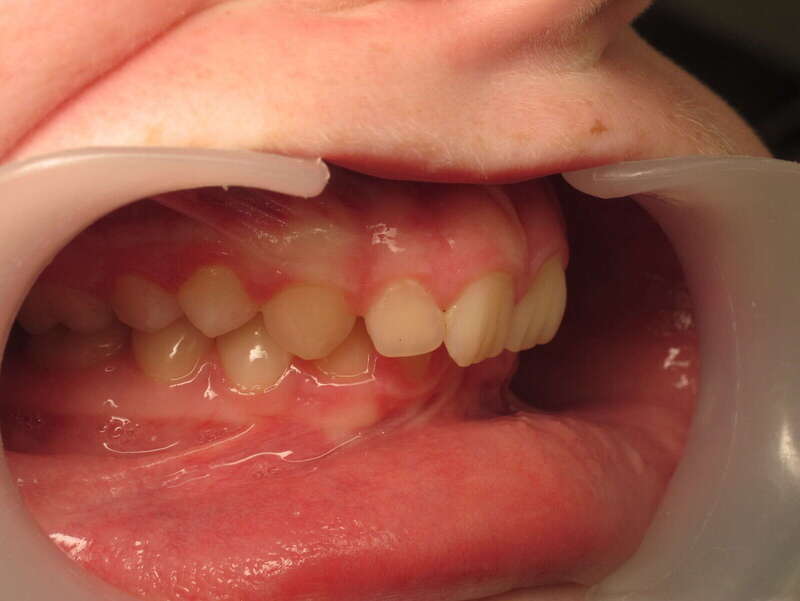

Cas n°1 traité par aligneurs (interception) - enfant

Ce cas d’interception chez un enfant de 8 ans démontre l'efficacité des aligneurs pour corriger des troubles fonctionnels précoces. Le diagnostic présentait des inversions d'articulé provoquant une déviation de la mandibule vers la gauche et un décalage des milieux.

Grâce à une coopération exemplaire et un traitement totalement indolore, l'expansion de l'arcade a permis de recentrer la mâchoire. Cette intervention a littéralement remis la croissance sur les rails, neutralisant le risque d'asymétrie faciale squelettique.

Avant